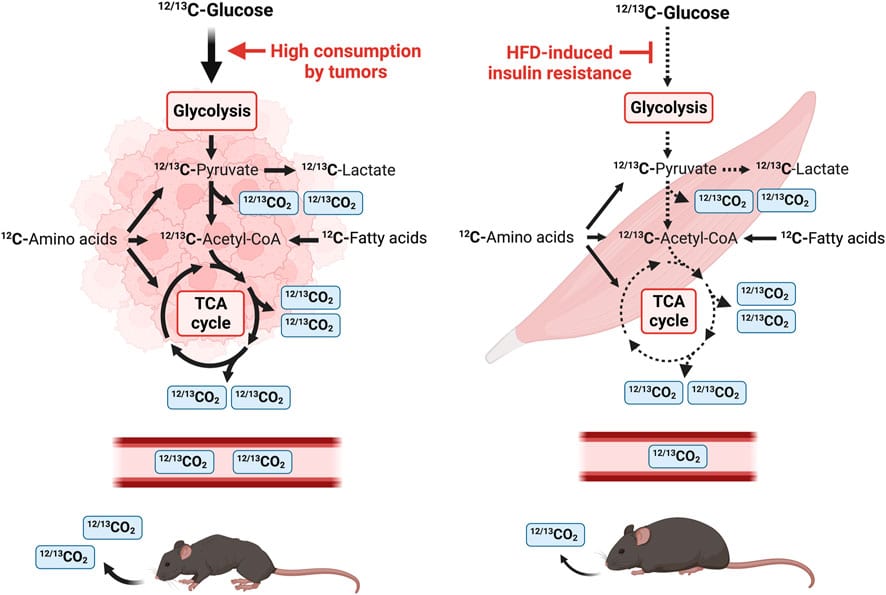

¹³CO2 isotope tracing combined with real-time indirect calorimetry reveals enhanced aerobic glycolysis in cancer and disrupted glucose utilization in diet-induced obesity (DIO).

Metabolic rewiring is a hallmark feature prevalent in cancer cells and insulin resistance (IR) associated with diet-induced obesity (DIO).

Metabolic rewiring is one of the hallmarks of cancer that promotes tumor proliferation in low-nutrient and oxygen conditions. Metabolic reprogramming includes the Warburg effect or aerobic glycolysis and the recycling of lactate, amino acids, and ammonia to support cancer cell growth and progression. Interestingly, lactate is the primary fuel source of the mitochondrial tricarboxylic acid (TCA) cycle in the human lung and many other tissues (references in the paper). The Warburg effect has been demonstrated in most tumors and, in clinical applications, has been leveraged for imaging, such as fluoro-D-glucose Positron Emission Tomography (18F-FDG-PET) to detect glucose uptake in tumors. Studies from humans and mice show that increased glucose and lactate oxidation in the Mitochondria is characteristic of the altered metabolism of lung tumors and other tumor types.

Glucose homeostasis is also disrupted in metabolic syndrome, obesity, and type 2 diabetes. Consumption of high-fat and high-sugar diets is one of the major causes of DIO and is attributed to IR, which is characterized by elevated blood glucose and triglyceride levels.

For the first time, the data in this study show real-time elevated tracer ¹³CO2 expired by tumor-bearing (TB) mice and a reduction in exhaled ¹³CO2 in the DIO model. These findings illustrate high glucose uptake and consumption in TB animals and decreased glucose uptake and oxidation in obese mice with an Insulin resistance (IR) phenotype.

Schematic diagram of a stable isotope breath test study in mice using U-13C glucose.